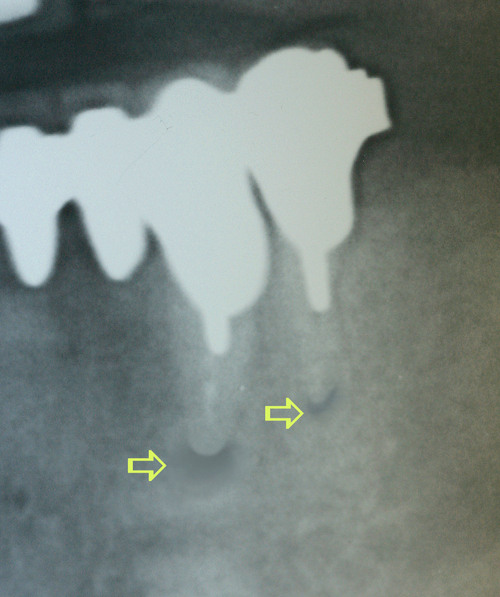

Cet acte simple donne de très bons résultats lorsque le canal peut être facilement désobturé. Les suites opératoires sont indolores et la cicatrisation osseuse est visible en quelques mois (fig.17).

fig. 17 – la guérison osseuse est obtenue en 2 mois